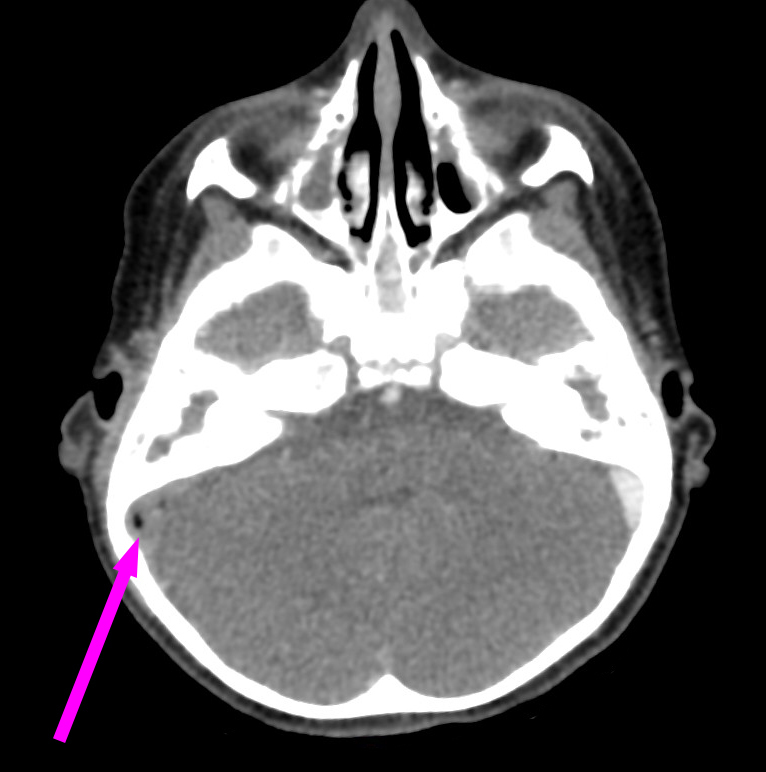

Voici l’imagerie que vous avez demandée. Devant le tableau, le radiologue a également choisi de faire une IRM.

Question 13 : Qu’en pensez-vous ?

Confirmée par la présence d’abcès sous-cutanés rétro-auriculaires droits (cf. question 4)

On voit bien une image plurilobée d’abcès à droite

On peut voir sur le scanner une image très hypodense dans le sinus à droite (alors que le sinus gauche est normalement hyperdense). C’est très visible sur la coupe en IRM avec un caillot hypo-intense au milieu du sinus veineux à droite

Comme expliqué à la question précédente, l’intérêt est de chercher les complications intracrâniennes. Il n’y a pas ici d’abcès intracrânien, mais on retrouve une thrombophlébite importante du sinus sigmoïde droit. Insérer image « Figure10.jpg ». Insérer image « Figure11.jpg ». Insérer image « Figure12.jpg »